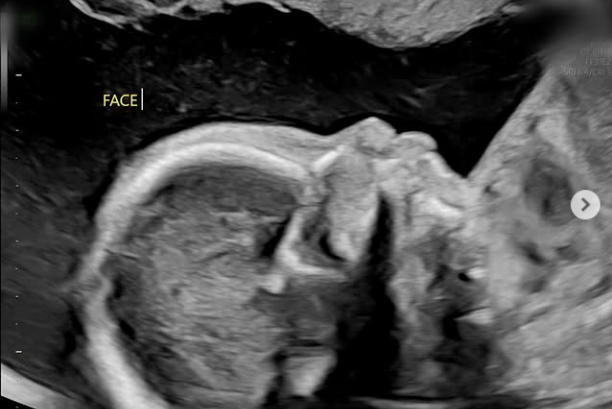

남보라는 지난 15일 자신의 소셜미디어를 통해 "22주 정밀 초음파 보고 왔다. 어느새 훌쩍 자라버린 콩알이. 이제 콩알이 아니고 휴먼(사람)입니다"라는 글과 함께 여러 장의 사진을 게재했다.

공개된 사진 속에는 어느덧 훌쩍 자란 아이의 정밀 초음파 모습과 함께 눈에 띄게 선명해진 남보라의 'D라인'이 담겨 눈길을 사로잡았다.